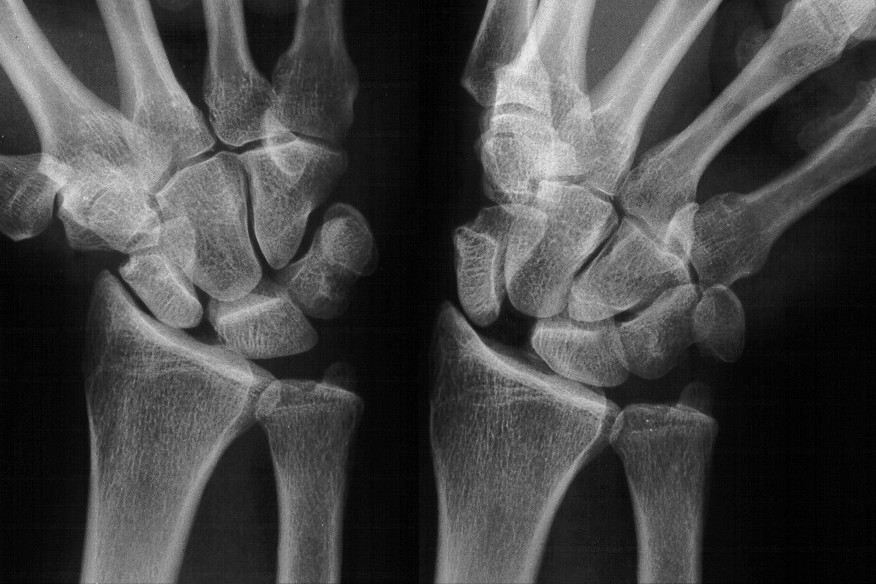

Case 1. Chronic complete scapholunate ligament disruption seen on MRI

Click for larger image

Palmar flexion of the scaphoid, lunate dorsiflexion.

Scapholunate diastasis.